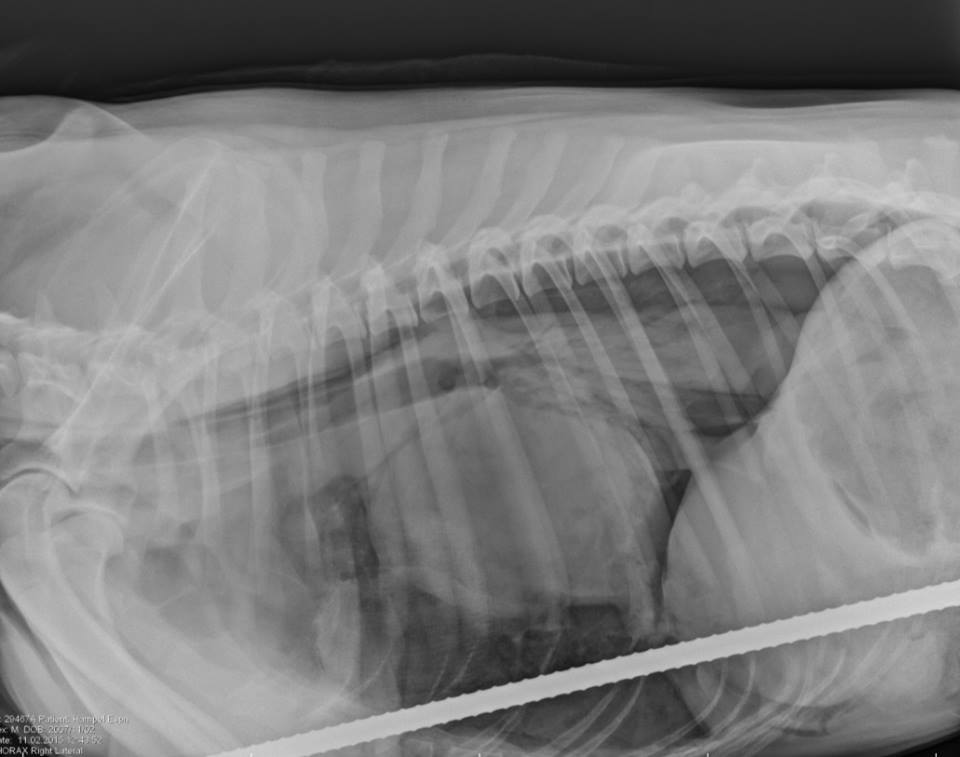

According to Espen’s x-ray, the rod punctured his lung and diaphragm, and also nicked his liver.

x-rayvia Hope Advanced Veterinary Care on Facebook